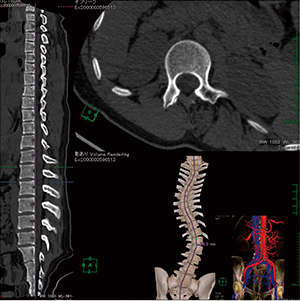

CPR表示機能は,3つのMPR画像から最適な画像で点をとり,中心線推定やスラブ厚調整などを行うだけで彎曲部分を平面的に,またストレート表示でも観察でき,プラークや石灰化などの狭窄箇所をわかりやすく観察することができる。

ASO(閉塞性動脈硬化症)治療後のステント内狭窄における血流形態・狭窄評価(図8)と,脊柱側彎症の手術前検査におけるO-armシミュレーション用の形態評価・血管走行確認(図9)の画像を示す。

図9 脊柱側彎症術前評価 |